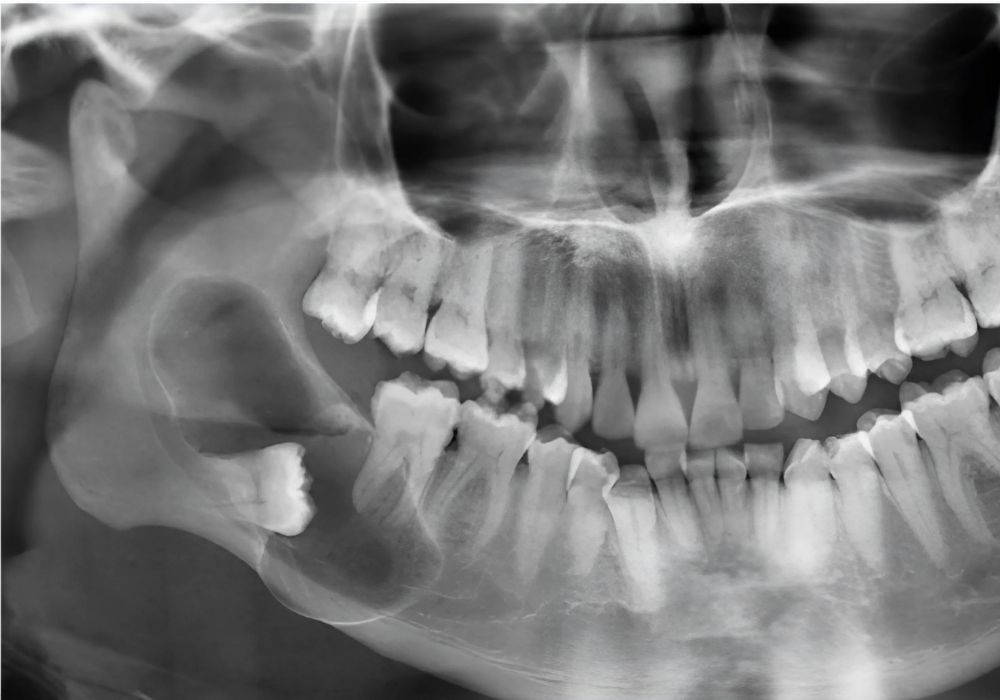

Dr Alexandru BARNA - Dentiste Granville - lesion apicale

La kystectomie dentaire est une intervention chirurgicale qui consiste à retirer un kyste formé autour d’une dent ou dans l’os de la mâchoire. Ce type de lésion est souvent lié à une infection chronique ou à une dent non traitée, et peut rester longtemps silencieux avant de provoquer douleurs ou complications.

• Présence d’un kyste péri-apical détecté à la radio

• Kyste évolutif menaçant les dents voisines ou l’os

L’intervention consiste à soulever délicatement la gencive pour accéder au kyste, puis à retirer la totalité de la lésion sans fragiliser l’os. En fonction de la taille, une résection apicale peut être associée si la dent concernée est conservée.